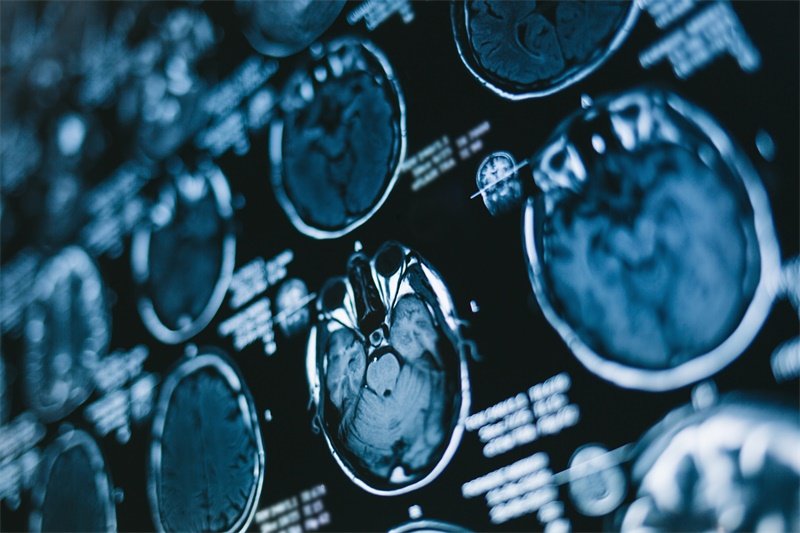

蝶鞍占位病变是指在蝶鞍区域内出现的异常结构,这可能是由肿瘤、囊肿或其他病变引起的。常见的病变包括垂体腺瘤、脑脊液囊肿等。这些病变可能导致蝶鞍的形状和体积发生改变,进而影响垂体的正常功能,产生一系列内分泌失调症状。

例如,垂体腺瘤可以导致多种内分泌疾病,如库欣症或巨人症。这类病变往往需要通过影像学检查和组织活检进行确诊。了解蝶鞍区域的解剖和功能特点,有助于医生更快地识别和处理这些病例。

垂体腺瘤的诊断通常依赖于影像学检查,如MRI或CT扫描。这些工具能够帮助医生发现任何结构上的异常。一旦确诊,治疗方案可能包括药物治疗、放疗或手术,具体的选择依赖于腺瘤的类型和患者的具体情况。因此,尽早就医非常关键。